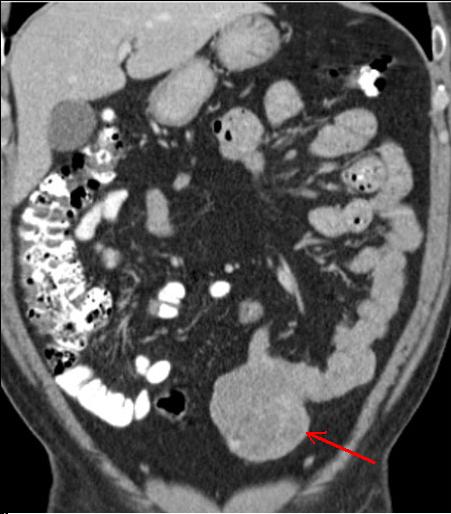

| Tumeur de GIST a distal de

ileon , image homogene a hypo-dense , poly lobulaire

et extraluminale . Image TDM en coupe coronal . |